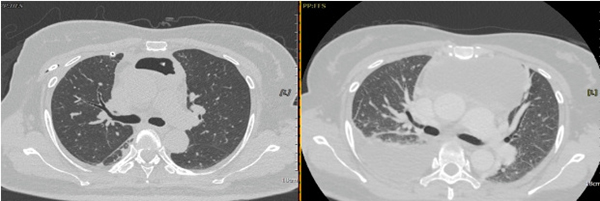

胸外科主任崔健在充分了解患者病情后,对病情进行了全面评估,即刻联系放射科安排CT引导下前纵膈肿物穿刺术,抽吸出黄色脓性坏死物,确诊疾病为“纵膈脓肿”,并指示病情危重,需进行急诊手术治疗,迅速联系麻醉科。在麻醉科的大力配合下即刻开展了手术。由于患者纵膈脓肿合并右侧脓胸,单纯纵膈清创引流不能解决右侧胸腔感染,遂决定在胸腔镜下行右侧脓胸清除术+前纵膈切开引流术。术中可见右侧胸腔大量脓性坏死物,吸出胸腔内脓液约650ml,紧接着打开前纵膈,吸出脓性坏死物约200ml,后进行了彻底的冲洗,在紧锣密鼓的3小时手术后,患者平安返回病房,最终顺利出院。

▲术后/术前胸部CT对比